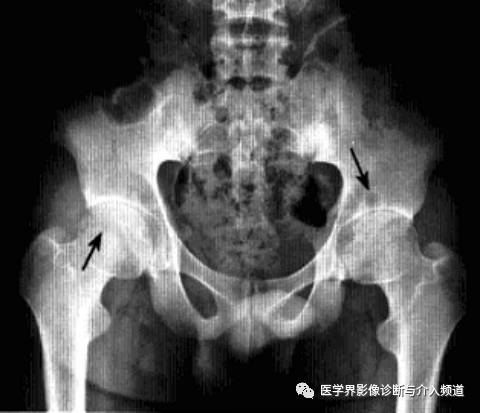

髋关节色素沉着绒毛结节性滑膜炎

一种侵及关节、腱鞘、滑囊或肌腱组织的良性增生伴色素沉着性病变。一般单关节发病,最常累及膝关节,其次是髋关节、踝关节、肩关节、肘关节。

病理:表面凹凸不平,有绒毛状滑膜皱襞覆盖,累及关节囊及周围软组织内血管和神经结构。

临床表现:以20-40岁青年女性多见,多有髋部外伤史,早期无特征,进展缓慢。

影像诊断:早期诊断缺泛特异性,晚期出现典型骨质破坏。MRI检查具较强特异性及定性诊断作用。